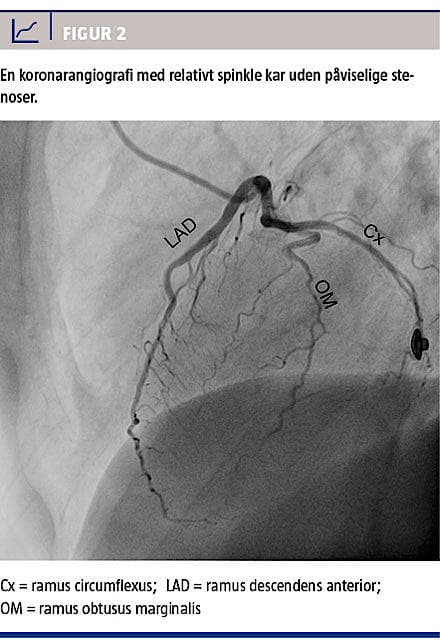

ST-depression (Figur 1). Paraklinisk var der et troponin-T-udslip på 593 ng/l (referenceværdi < 50 ng/l), hvorfor diagnosen non-ST-elevationsmyokardieinfarkt blev stillet. En ekkokardiografi viste let hypokinesi af den laterale del af venstre ventrikels forvæg, men samlet en normal uddrivningsfraktion på 60%. Dag 6 viste en koronarangiografi relativt spinkle kar uden angiografisk påviselige stenoser (Figur 2). Ved udskrivelsen var troponin-T-niveauet faldende, betablokkeren blev skiftet til propranolol 40 mg × 2, og hun blev frarådet al brug af triptaner. Tre måneder efter indlæggelsen var hendes troponin-T-niveau og ekg normaliseret, og migræneanfaldene var ophørt.